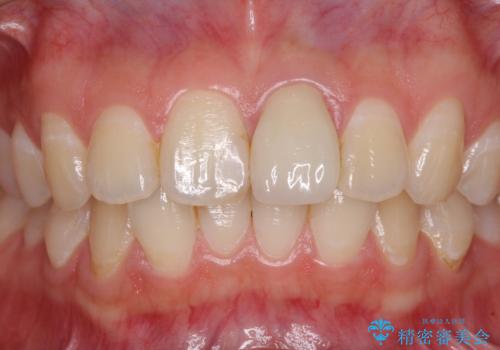

出っ歯に仕上がってしまった前歯 セラミッククラウンの作り替え

- 以前治療した時から、前歯のセラミックが張り出しているのが気になるとのことで来院された患者様です。

作り替えるべきが悩みましたが、どうしても気になるとのことで、処置を行うこととしました。

前歯1歯でのオールセラミッククラウンでは、オーダーメイドタイプのクラウンを選択していただき、周辺の歯と色調を合わせるようにするのですが、今回は既製タイプを選択されました。